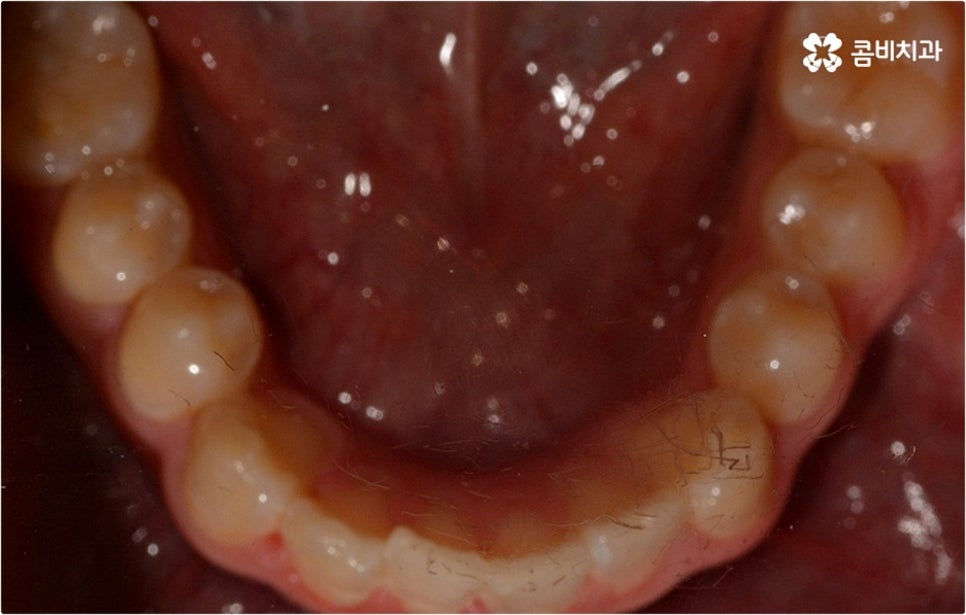

출처 아카이브 열기웃을 때 살짝 드러나는 덧니는 사람에 따라 매력 포인트로 느껴지는 경우도 있지만 구강 건강 측면에서 보면 치아와 치아가 겹쳐진 부분에 음식물 찌꺼기가 남아 치석이 쌓이기 쉽기 때문에 충치나 잇몸병이 더 자주 발생할 수 있으므로 주의하실 필요가 있습니다. 이와 같이 덧니는 옆 치아와 잇몸에까지 지속적으로 좋지 않은 영향을 주기 때문에 개선해 주는 게 좋은데요, 특히 덧니의 개수가 많아 삐뚤빼뚤한 정도가 심하다면 교합이 잘 맞지 않아 씹기가 불편하거나 턱관절 압박, 통증 등을 유발할 수 있으며 나아가 안면비대칭으로 이어질 수 있기 때문에 방치하지 말고 될 수 있는대로 빨리 덧니교정 을 통해 이를 바로잡아 주시길 권유드리고 있습니다.

덧니의 원인에는 여러 가지가 있을 수 있으나 보통 혼합치열기, 즉 유치가 영구치로 교체되면서 둘이 공존하는 시기인 6~13세 사이에 교체가 원활하게 이루어지지 않는 것 (유치가 너무 빨리 빠져 충분한 공간 유지가 되지 않거나 너무 늦게까지 빠지지 않아 영구치와 겹쳐 나게 됨), 선천적으로 치아가 나올 공간이 부족하거나 영구치가 너무 크게 자라는 것 등을 원인으로 발생하는 경우가 많아 초등학교 고학년에서 중학교 저학년까지의 시기를 덧니교정 치료를 위한 정밀 검진의 골든 타임으로 여기고 있습니다.

덧니교정 시 환자분들의 상황에 따라 치아 이동에 필요한 공간이 부족하지 않다면 비발치 교정이 가능한데요, 이런 경우 치아 사이를 살짝 갈아서 여유 공간을 만드는 치간 삭제 방법, 마지막 어금니를 후방으로 이동시키는 방법, 그리고 악궁 확장 장치를 사용해 치아 사이를 벌려주는 방법 등 다양한 방법으로 공간을 만들어 치열을 가지런하게 바로잡아 줄 수 있습니다. 이때 환자분들의 구강 상태, 즉 악궁 크기 대비 치아의 크기, 치아가 겹친 정도, 덧니의 위치와 개수 등을 자세하게 검진한 다음 치아가 이동할 충분한 공간이 확보되지 않는다면 발치 교정을 하게 될 거예요.